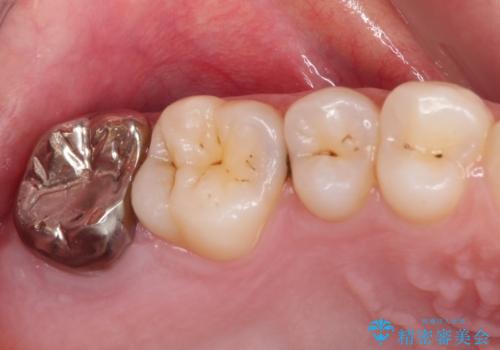

歯ぐきの形を整え、外れにくい被せ物を装着

歯の高さを出すための親知らず抜歯と歯肉切除

担当医 岡田康成